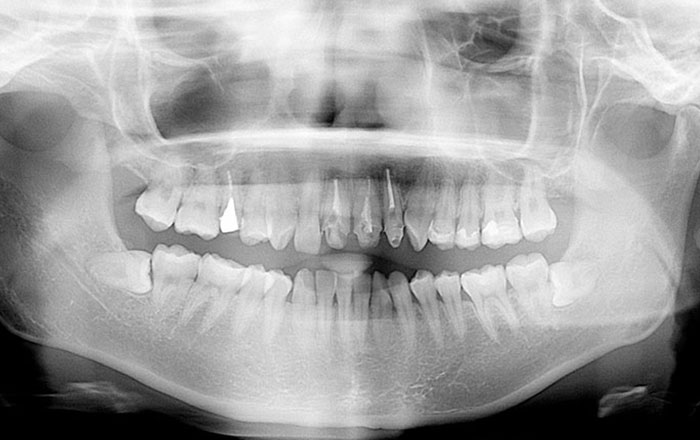

親知らず抜歯は、まずはX線で状態を確認してから行うので、来院してすぐ、いきなり抜歯することはありません。